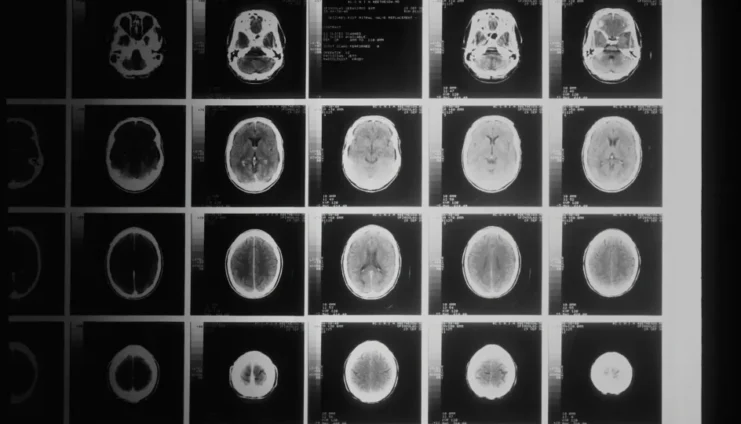

Analizējot vairāk nekā divarpus tūkstošus magnētiskās rezonanses izmeklējumu, pētnieki pamanīja skaidras atšķirības starp cilvēkiem ar veselu nervu sistēmu un tiem, kuru kognitīvās spējas jau bija pavājinātas. Šie atklājumi dod pamatu cerēt, ka smadzeņu ģeometrija var kļūt par jaunu un efektīvu medicīnisku rīku.

Pētījums maina līdzšinējo priekšstatu par smadzeņu novecošanos – izšķirošs ir ne tikai apjoms, bet arī forma. Smadzeņu virsmas ģeometrija ļauj pamanīt ļoti smalkas pārmaiņas, kas notiek ilgi pirms pirmajiem simptomiem. Tas dod cerību, ka nākotnē smagas smadzeņu saslimšanas būs iespējams konstatēt daudz agrāk.